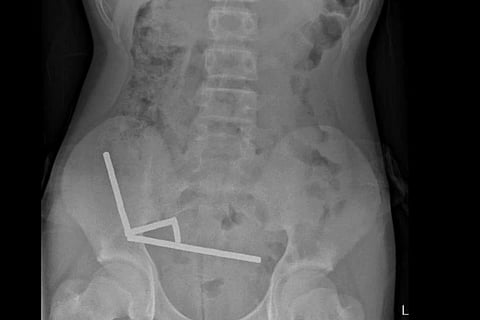

Scans showed that the magnets had formed four chains inside his abdomen, binding parts of the bowel together.